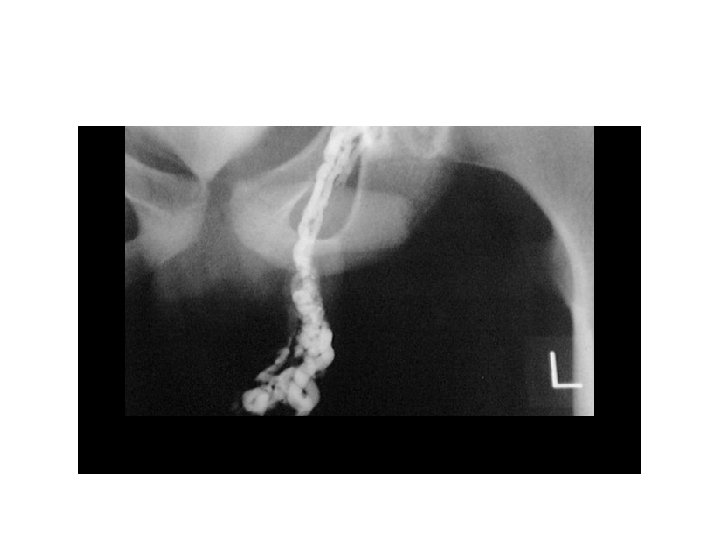

Görüntüleme • • • Doppler USG (En sık kullanılan) BT Venografi (En değerli) Radyonükleid anjiografi Skrotal termografi